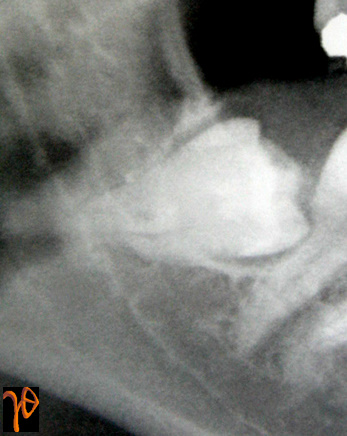

Στις εικόνες που ακολουθούν υπενθυμίζονται κάποιες από αυτές τις περιπτώσεις στις οποίες θα πρέπει να δίνεται ιδιαίτερη προεγχειρητική και χειρουργική προσοχή:

Εικόνα 1. Απόκλιση των ριζών [Σχέδιο (1) και Ακτινογραφίες (α) και (β)], Στένωση του Πόρου [Σχέδιο (2) και Ακτινογραφίες (β) και (γ)]